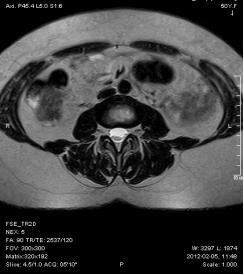

4, 腰椎间盘突出